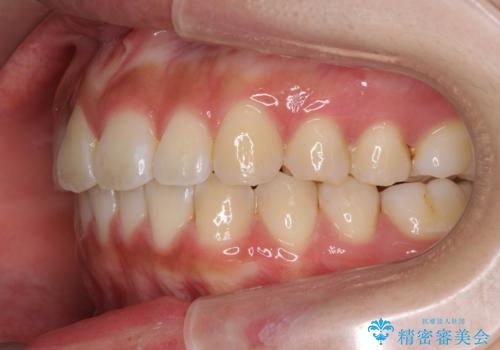

- 前歯の目立つねじれを矯正治療で治したい、と来院されました。

マウスピース矯正を始める前に、ねじれを取るのが短期間で済む部分ワイヤー小矯正を行うことで、全体的な治療期間を短くする治療計画を実行していきます。

前歯のねじれはマウスピース矯正の苦手な動きになり、治療期間が長くなる原因になりやすいです。